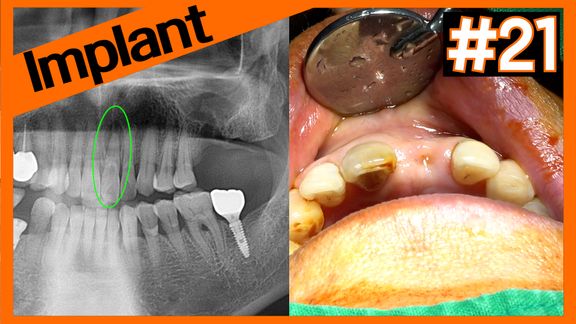

Impacted tooth vs. Implant